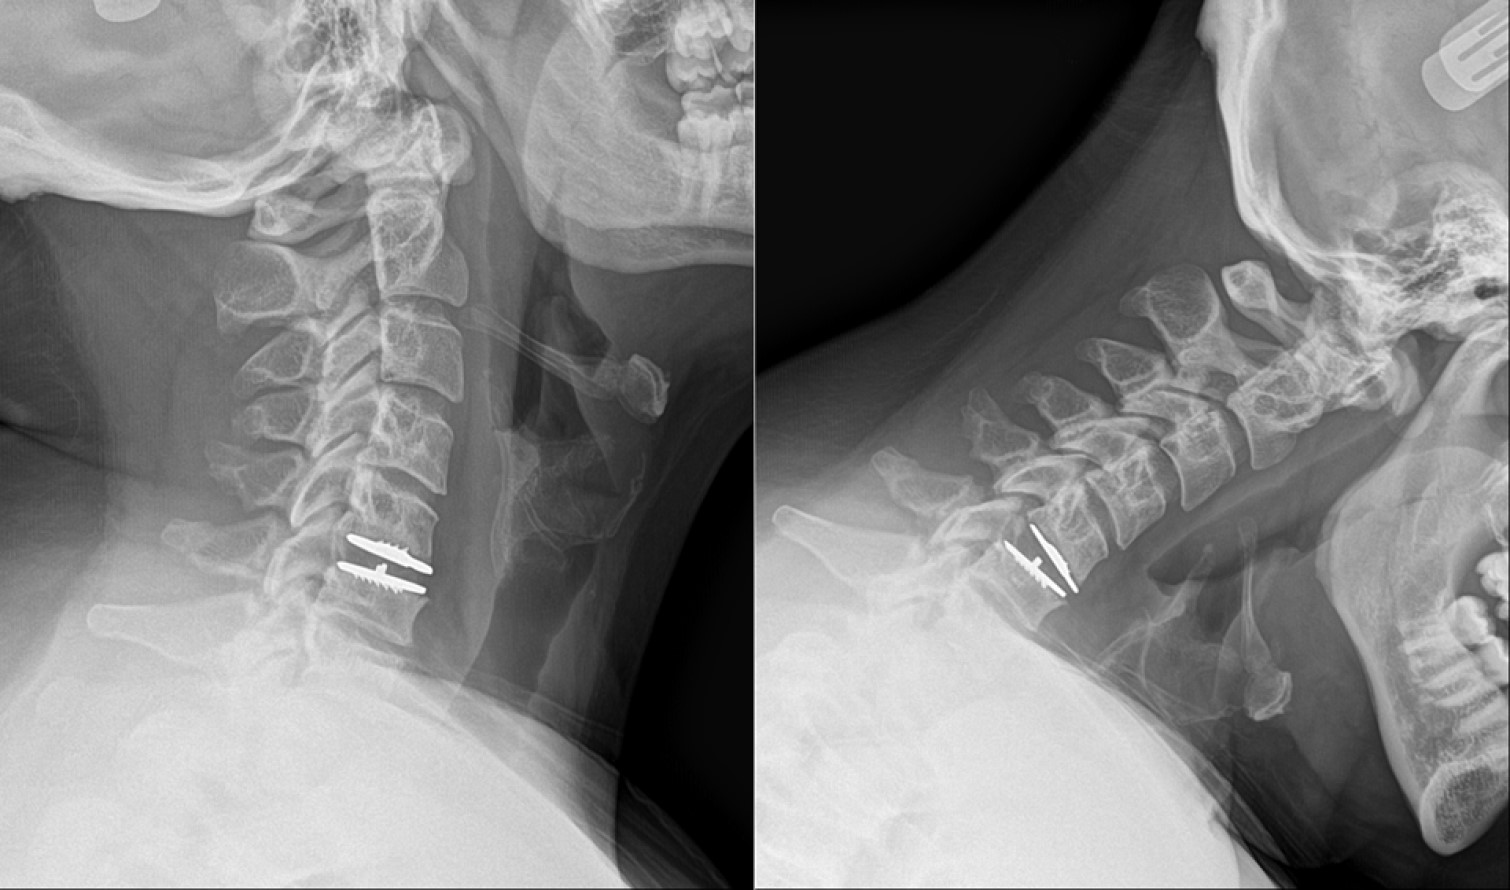

Preoperative cervical spine x-rays with extension (bending back, left) and flexion (bending forward, right) views of the cervical spine. Note the relatively focal degenerative changes at C5/6 (arrows) with lack of movement.